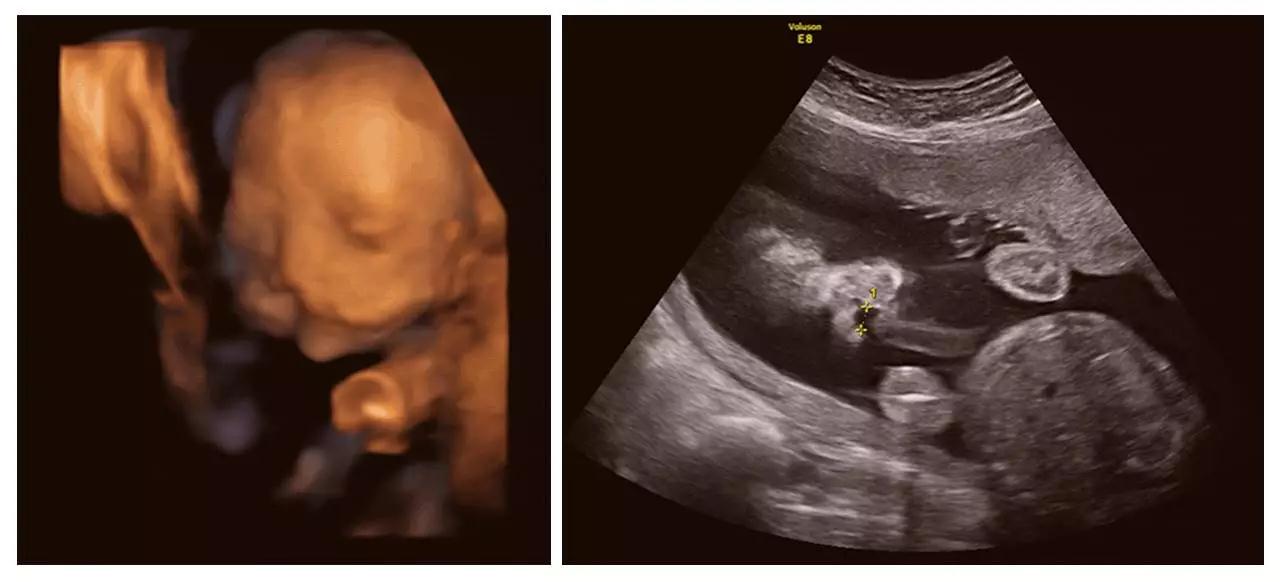

近日,美国一对宝宝在妈妈子宫里相拥亲吻的照片在网络疯传。据报道,美国准妈妈Carissa Gill非常期待自己双胞胎女儿们的到来,所以对她们的四维照片特别着迷,而最近一次孕检,让她有更为惊喜的发现。

在Carissa怀孕25周的一次孕检中,她在四维彩超(四维彩超)视频中发现,自己的一个女儿首先亲吻了另一个女儿的胸口,然后她们慢慢接近,最后竟然相互用嘴亲吻!

夫妇俩给两个女儿取名为Isabella和Callie。妈妈Carissa把图像照片上传到了社交网站上。她在其中一张照片中写道,Isabella在姐姐Callie的脸颊上印了一个吻。在另一张照片中,她写道,在这一刻她很感恩,迫不及待地想要认识这两位珍贵的公主。

正是通过神奇的四维彩超(四维彩超),我们一起见证了这有爱的一幕。四维彩超(四维彩超)的出现对于妇产科学界意义重大,在探头下,我们可以清晰地看见宝宝的动态,看见宝宝发育的情况。不仅如此,四维彩超(四维彩超)能通过清晰的画面对胎儿的体表进行检查,及早发现唇裂、脊柱裂,大脑、肾、心脏、骨骼发育不良等各种畸形情况,检测和发现各种异常。简单的说,四维彩超(四维彩超)的作用,就是从零岁起监测宝宝的发育情况,保障每一个新生儿的健康!

济南艾玛妇产医院作为山东首家 JCI 金牌妇产专科医院,在今年年初,又顺利成为济南市基本医疗保险定点医疗单位,集医疗安全和客户就诊的便捷度于一体。济南艾玛妇产医院一直非常重视围产期保健及宝宝出生缺陷的预防,率先引进美国GE-E8高清四维彩超(四维彩超)设备,从0岁开始守护宝宝的健康,见证宝宝的成长。